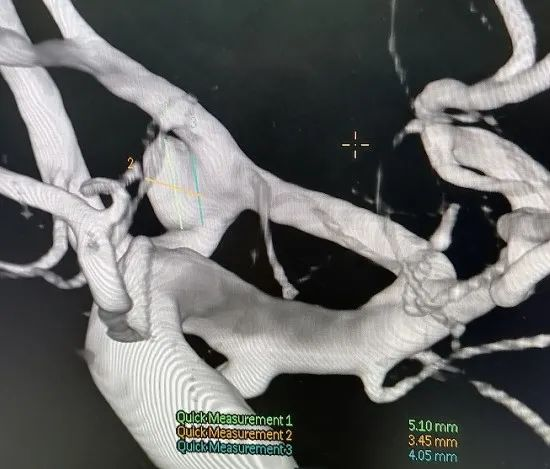

2020-11-30胡翠芹 左侧颈内动脉眼段动脉瘤支架辅助弹簧圈栓塞术